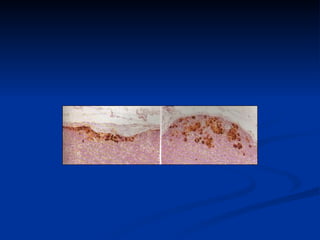

El documento describe el concepto de ganglio centinela en el tratamiento del melanoma. Explica que el ganglio centinela es el primero en recibir el drenaje linfático de un tumor primario. Su biopsia permite determinar si el cáncer se ha propagado a los ganglios linfáticos regionales sin necesidad de disecciones más amplias, reduciendo la morbilidad. Los candidatos ideales son pacientes con ganglios clínicamente negativos y Breslow mayor a 1mm u otros factores de riesgo con Breslow menor. La biopsia